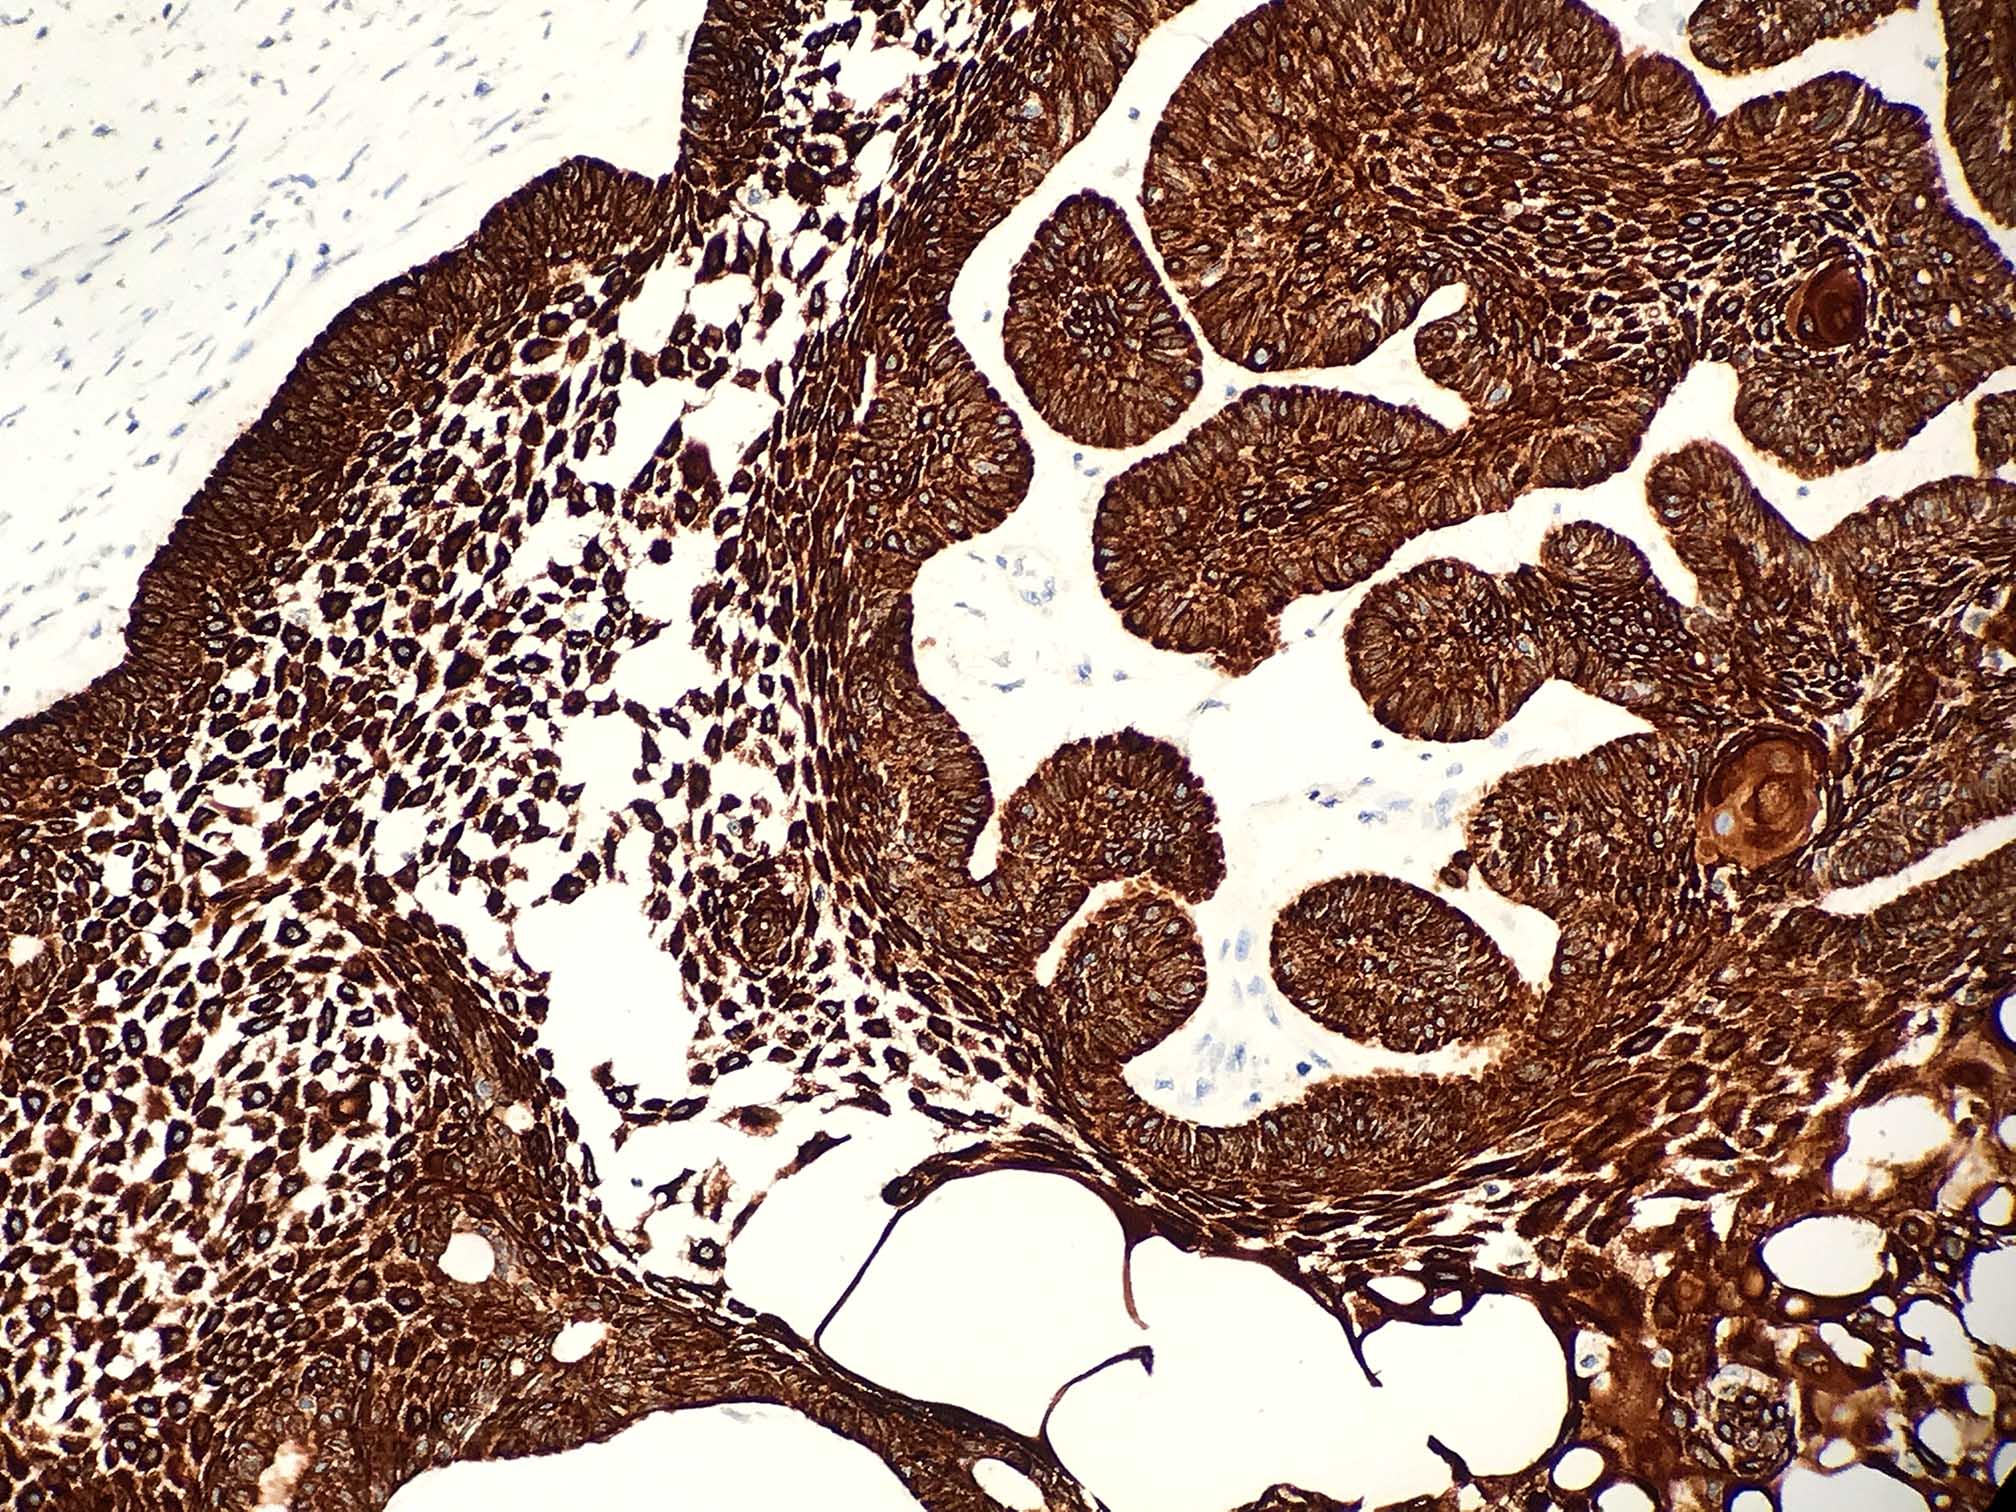

Microscopic (histologic) images

Contributed by Kelly Magliocca, D.D.S., M.P.H. and Anne C. McLean-Holden, D.M.D., M.S.

Microscopic (histologic) description

- Within the epithelial islands and cords of conventional ameloblastoma and the cystic epithelial lining of unicystic ameloblastoma, the odontogenic epithelium shows similar changes:

- Columnar cells with hyperchromatic nuclei at basal layer, exhibiting peripheral palisading

- Cells show reverse polarization away from basement membrane (Vickers-Gorlin change)

- Subnuclear vacuolization

- Suprabasal cells with a loose, network-like arrangement, recapitulating stellate reticulum formation seen in normal odontogenesis

- Ameloblastoma, conventional type has at least 6 histopathological patterns

- Follicular: most common subtype; islands of odontogenic epithelium in fibrous connective tissue; may be cystic; classic peripheral palisading and stellate reticulum-like areas

- Plexiform: cords and sheets of anastomosing odontogenic epithelial cells; classic peripheral palisading and reverse polarity not always obvious